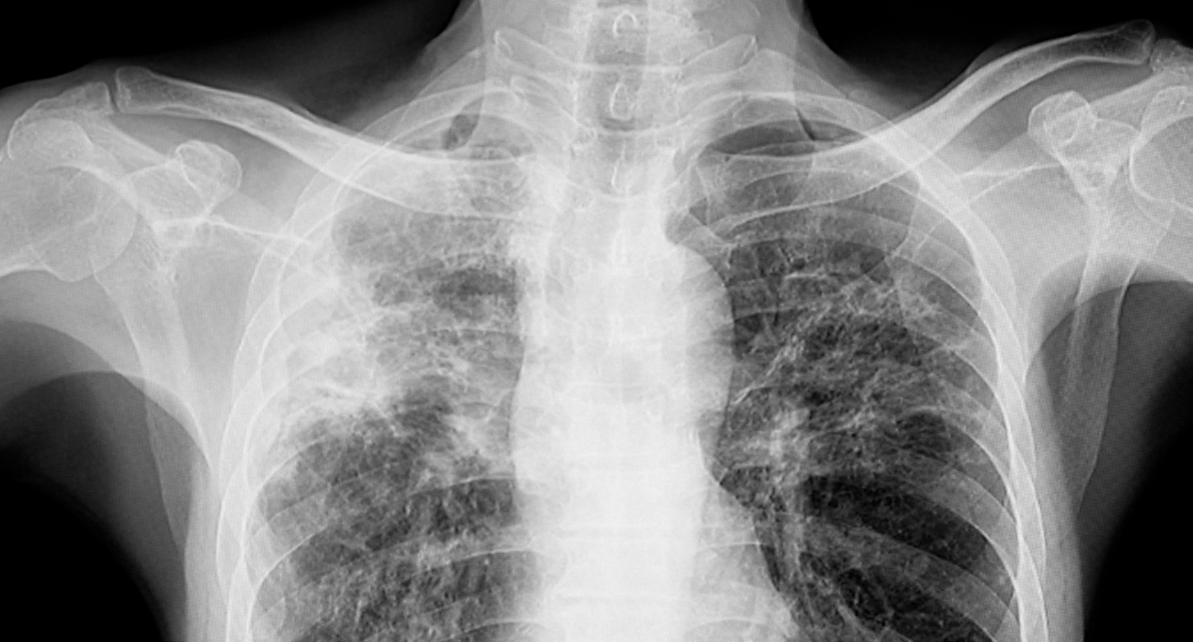

TB is an infectious disease caused by bacteria, predominantly spread by coughing. The disease most commonly affects the lungs but also infects and has an impact on other parts of the body, including the spine and brain.

Right now, East London has one of the highest numbers of newly diagnosed cases of TB in Western Europe. This rate of diagnosis is often linked to social deprivation. Barts Health manages 5-6% of TB cases nationally. In 2024, that was 294 patients - and by the end of July 2025 they saw a 37% rise in cases.